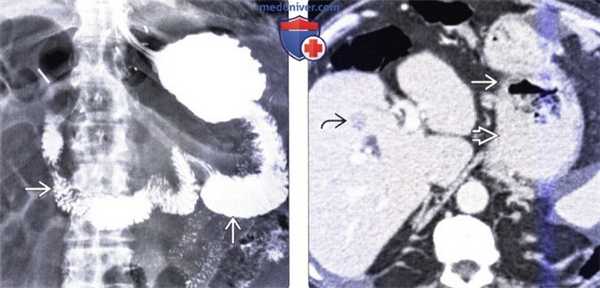

(Слева) На рентгенограмме, полученной после 30-минутной задержки при исследовании пассажа бариевой взвеси по тонкой кишке пожилому мужчине, перенесшему резекцию желудка по Бильрот 2 по поводу доброкачественной язвенной болезни 15 лет назад, определяется, что контраст поступает преимущественно в приводящую петлю, в то время как отводящая петля заполняется контрастом в меньшем количестве и с задержкой.

(Справа) На аксиальной КТ с контрастным усилением у этого же пациента определяется расширение просвета и утолщение стенки культи желудка возле желудочно-тонкокишечного анастомоза, обусловленное раком желудка. Визуализируется также метастаз в печень.

(Слева) На аксиальной КТ с контрастным усилением у этого же пациента определяется выраженная брыжеечная лимфаденопатия в результате лимфогенного метастазирования опухоли.

(Справа) На аксиальной КТ с контрастом у этого же пациента визуализируется большая опухоль в брыжейке, обрастающая отводящую петлю. Виден также просвет приводящей петли, заполненный контрастом. Частота возникновения рака желудка увеличивается после оперативного вмешательства по Бильрот 2, особенно спустя 15 и более лет.